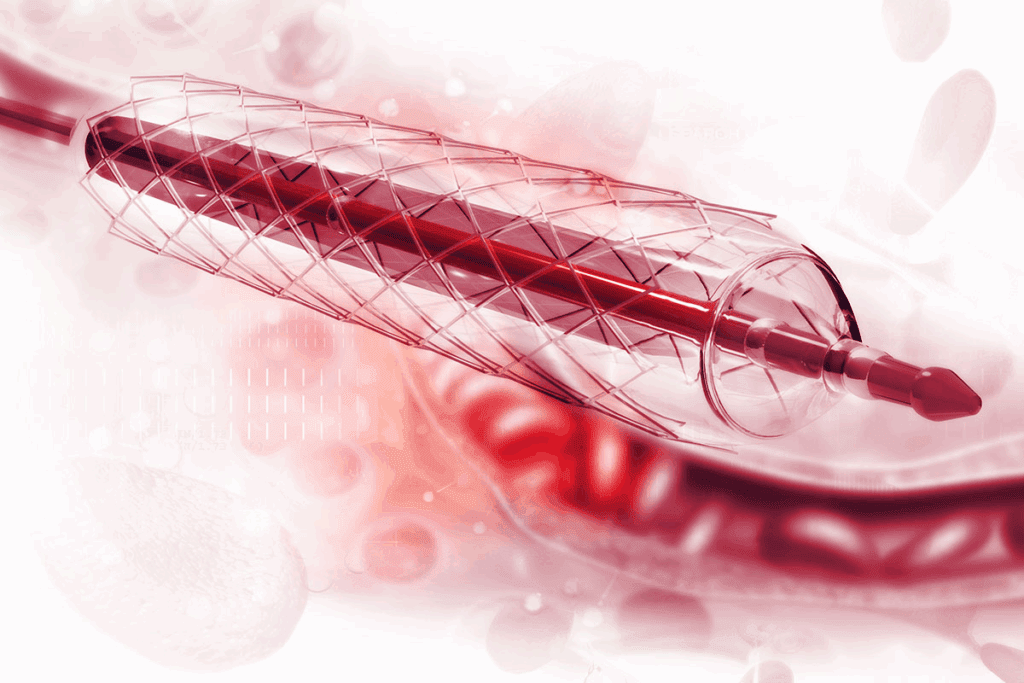

RFA uses radio waves to heat up and stop nerves. This method blocks pain signals to the brain. A special needle delivers the energy to the nerves.

RFA targets and stops pain nerves. A doctor uses X-rays to guide a needle to the nerves. Then, radio waves heat up the nerve, stopping it from sending pain signals.

“Burning nerves” in back pain relief is a precise medical technique called radiofrequency ablation (RFA). It uses radiofrequency energy through a needle to heat and disrupt pain-signaling nerves. This gives relief to those with chronic back pain.

Radiofrequency ablation heats nerves with radiofrequency waves. This heat stops the nerves from sending pain signals to the brain. This leads to less or no pain.

To start, a special needle electrode is placed near the nerve under imaging. The electrode sends out radiofrequency energy. This heats the tissue around the nerve, stopping it from working. This precision in targeting makes RFA different from other pain treatments.